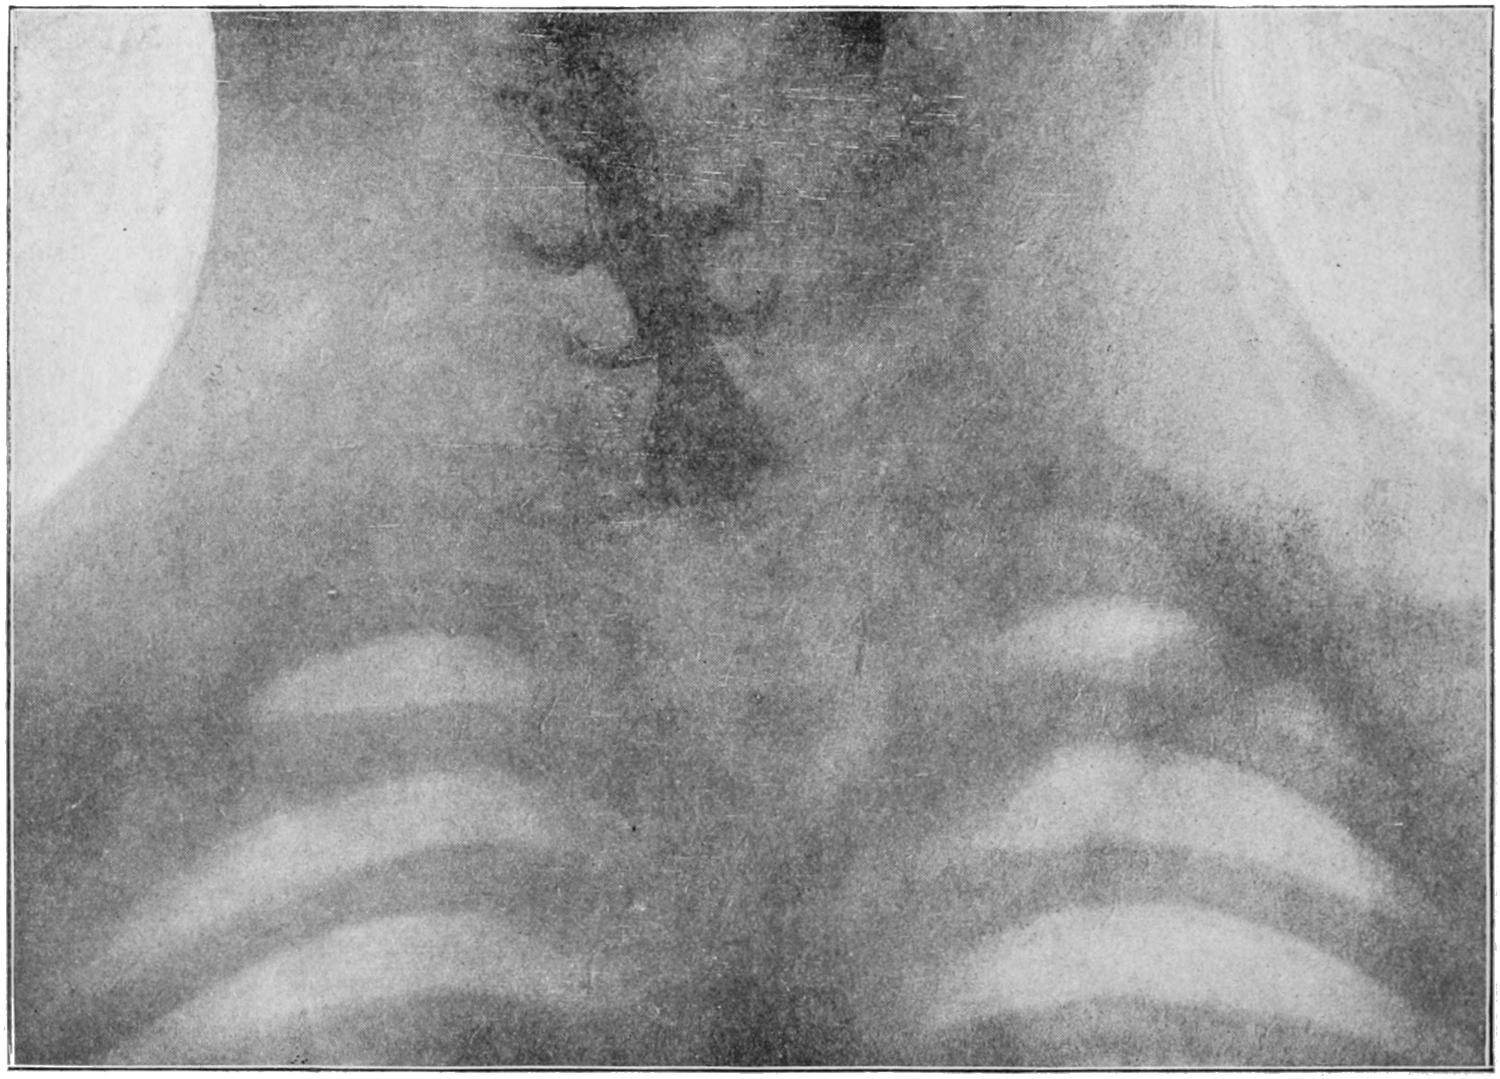

PLATE I

Fig. I.

Fig. II.

Fig. III.

Fig. IV.

Fig. V.

Fig. VI.

Fig. VII.

Fig. VIII.

DRAWN BY J. N. Z. CHASE

PLATE I.

BLOOD.

(Ehrlich triple stain.)

(Prepared by Dr. I. P. Lyon.)

Fig. I. TYPES OF LEUCOCYTES.

a. Polymorphonuclear Neutrophile. b. Polymorphonuclear Eosinophile. c. Myelocyte (Neutrophilic). d. Eosinophilic Myelocyte. e. Large Lymphocyte (large Mononuclear). f. Small Lymphocyte (small Mononuclear).

Fig. II. NORMAL BLOOD.

Field contains one neutrophile. Reds are normal.

Fig. III. ANÆMIA, POST-OPERATIVE (secondary).

The reds are fewer than normal, and are deficient in hæmoglobin and somewhat irregular in form. One normoblast is seen in the field, and two neutrophiles and one small lymphocyte, showing a marked post-hæmorrhagic anæmia, with leucocytosis.

Fig. IV. LEUCOCYTOSIS, INFLAMMATORY.

The reds are normal. A marked leucocytosis is shown, with five neutrophiles and one small lymphocyte. This illustration may also serve the purpose of showing the leucocytosis of malignant tumor.

Fig. V. TRICHINOSIS.

A marked leucocytosis is shown, consisting of an eosinophilia.

Fig. VI. LYMPHATIC LEUKÆMIA.

Slight anæmia. A large relative and absolute increase of the lymphocytes (chiefly the small lymphocytes) is shown.

Fig. VII. SPLENO-MYELOGENOUS LEUKÆMIA.

The reds show a secondary anæmia. Two normoblasts are shown. The leucocytosis is massive. Twenty leucocytes are shown, consisting of nine neutrophiles, seven myelocytes, two small lymphocytes, one eosinophile (polymorphonuclear) and one eosinophilic myelocyte. Note the polymorphous condition of the leucocytes, i. e., their variations from the typical in size and form.

Fig. VIII. VARIETIES OF RED CORPUSCLES.

a. Normal Red Corpuscle (normocyte). b, c. Anæmic Red Corpuscles. d-g. Poikilocytes. h. Microcyte. i. Megalocyte. j-n. Nucleated Red Corpuscles. j, k. Normoblasts. l. Microblast. m, n. Megaloblasts.

The value of a careful blood examination is well illustrated by Plate I, prepared by Dr. Irving P. Lyon, in which are displayed the alterations of greatest interest to the surgeon.